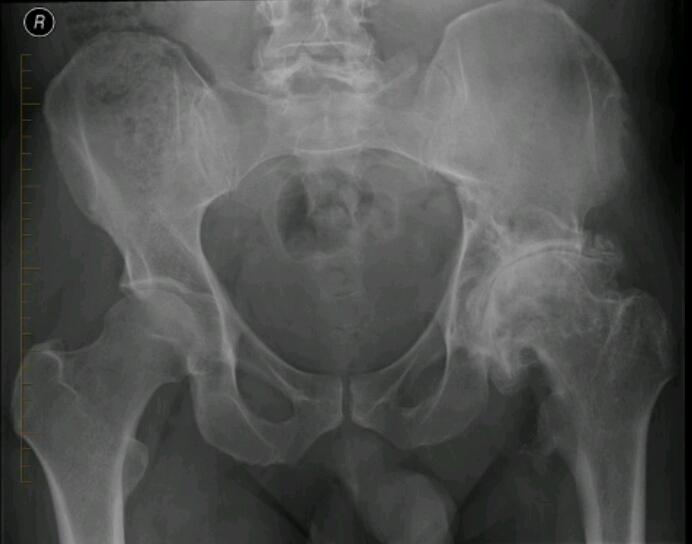

Name the disease. What are the signs of it?

Loss of superior joint space

Osteophyte formation

Subchondral cysts/geodes

Sclerosis

Buttressing

Joint deformity